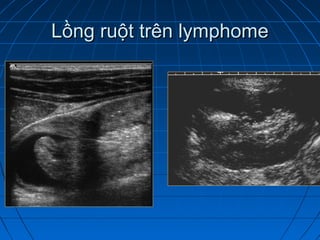

Lồng ruột trên lymphomeLồng ruột trên lymphome